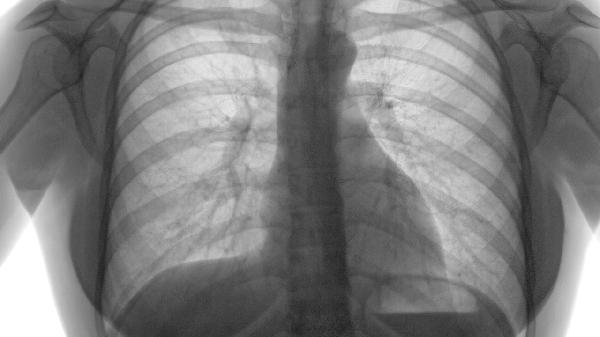

肺氣腫的治療方法主要有戒煙、氧療、藥物治療、肺康復(fù)訓(xùn)練、手術(shù)治療等。肺氣腫通常由長期吸煙、空氣污染、遺傳因素等原因引起,表現(xiàn)為呼吸困難、咳嗽、咳痰等癥狀。